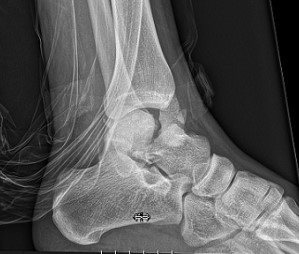

Пацієнти презентують з вираженим больовим синдромом у ділянці гомілковостопного суглоба, набряком, деформацією, обмеженням рухів та неможливістю опори на кінцівку. При вивихах можливе напруження шкіри з загрозою ішемічних ускладнень, що вимагає невідкладної репозиції. Критично важливим є оцінка нейроваскулярного статусу кінцівки, включаючи капілярне наповнення та чутливість.

Типовий вигляд стопи при травматичних пошкодженнях таранної кістки